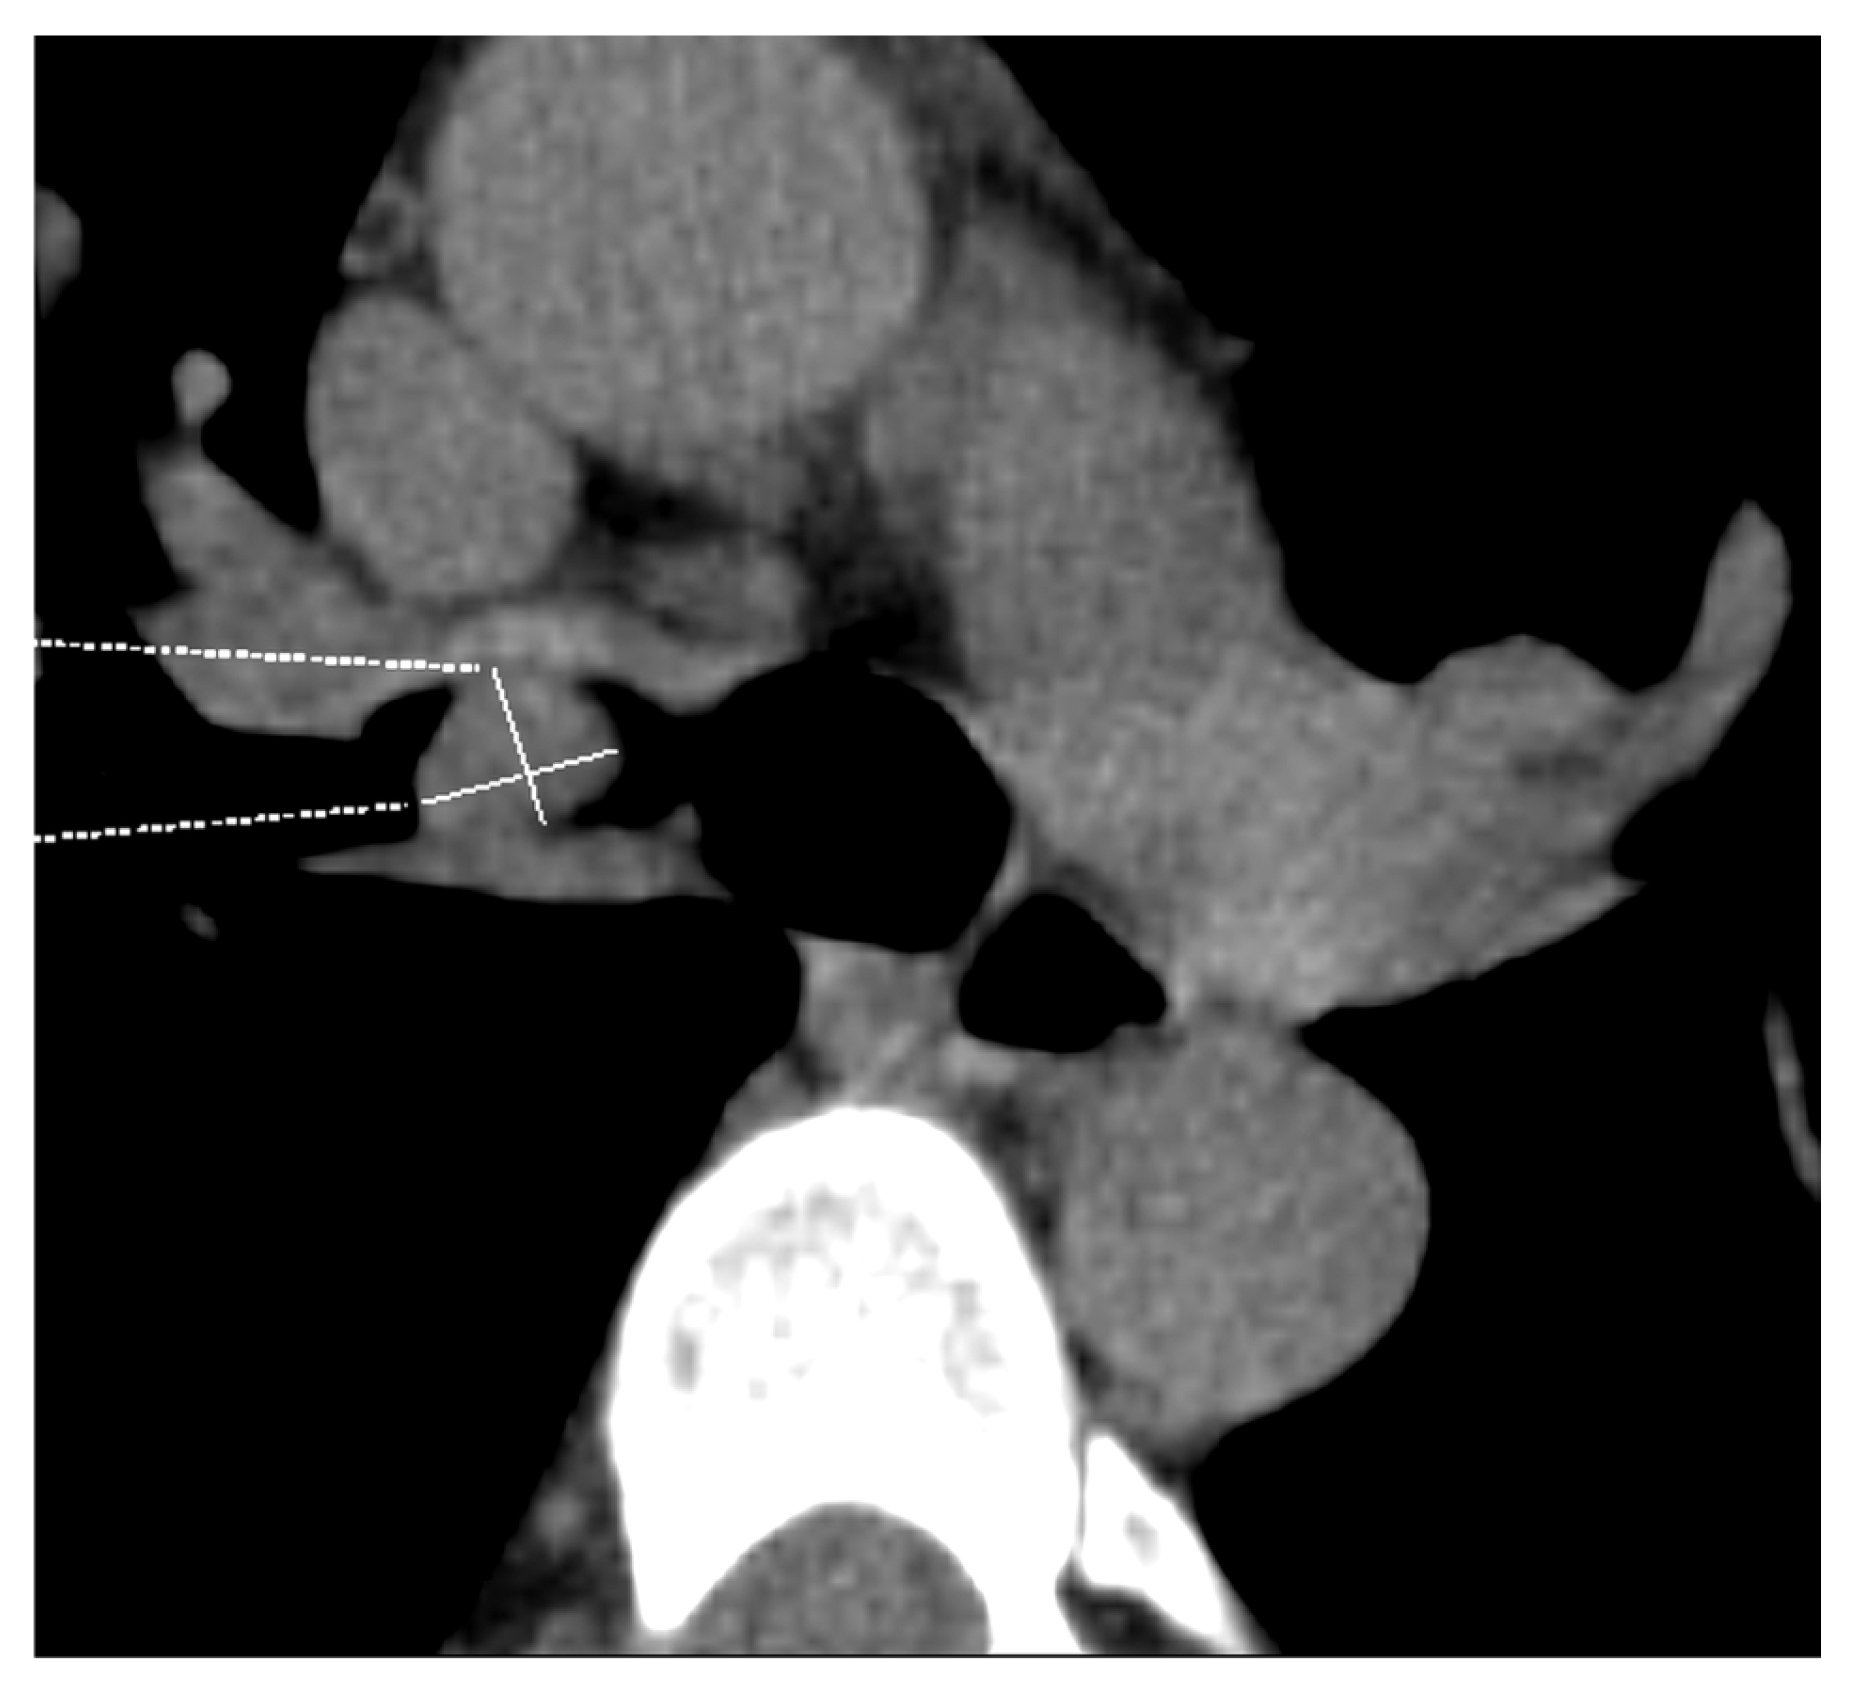

3.3. Involvement of the Main Bronchus, Carina, and Trachea

| T4 | Tumor > 7 cm in the greatest dimension Invasion of the mediastinum, thymus, trachea, carina, recurrent laryngeal nerve, vagus nerve, esophagus, or diaphragm Invasion of the heart, great vessels (aorta, superior or inferior vena cava, intrapericardial pulmonary arteries or veins), supra-aortic arteries, or brachiocephalic veins Invasion of subclavian vessels, vertebral body, lamina, spinal canal, cervical nerve roots, or brachial plexus Separate tumor nodule(s) in a different ipsilateral lobe than that of the primary | Signs of mediastinal invasion: infiltration of the mediastinal fat or structures that indicate the T4 stage, tumor–mediastinum contact length of more than 3 cm, an obtuse angle between the tumor and the mediastinum [37] Signs of vascular invasion: disappearance of the fat layer between the mass and the vessel, the angle between the mass and vessel wall >90°, a stenosis or deformation of the vascular lumen [41,42] |